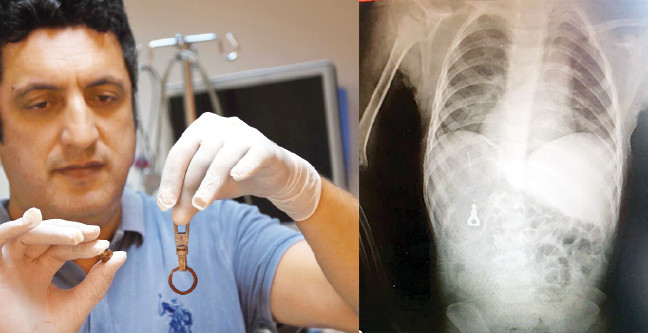

yer izmir doktorlar sok oldu

cocuklarin yuttugu cisimler saskina